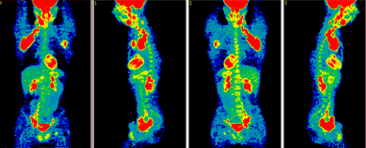

PET scans. Uptake of tracer in the lymph nodes involved with lymphoma in the groin, both axilla, and neck (red areas). Image courtesy of Dr. Jorge Carrasquillo, Nuclear Medicine Department, Clinical Center, National Institutes of Health

A PET scan is typically used to see cancer growing in the human body.  It works by injecting radioactive glucose into the body and seeing where it goes.  Where it lights up is where there is cancer. The PET scan measures metabolic activity. Cancer is known to use glucose as its primary energy source to grow, and it does this very efficiently. The cancer immediately grabs the glucose from your system, lighting up the scan.